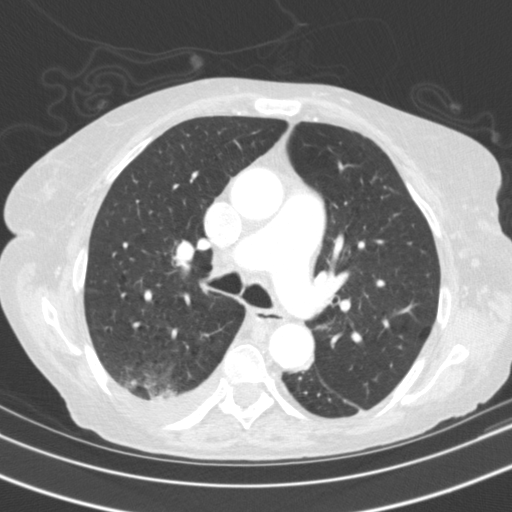

Generated VENOUS CT scan (A→B translation)

Full window (WL 1023.5, WW 4095 β†’ Low βˆ’1024, High +3071)

Lung window (WL -600, WW 1500 β†’ Low βˆ’1350, High +150)

Mediastinum window (WL 40, WW 400 β†’ Low βˆ’160, High +240)